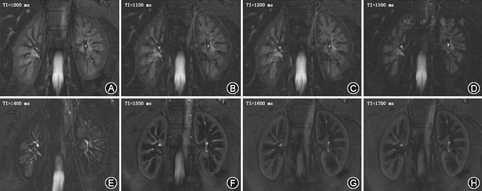

使用东芝3.0 T磁共振扫描仪以及体部相控阵线圈,附加呼吸门控装置,患者取仰卧位,头先进。反转恢复序列(inverse recovery, IR)、反转恢复时间(time of inversion, TI)的选取包括冠状位1 000、1 100、1 200、1 300、1 400、1 500、1 600、1 700 ms,在IR序列扫面前先行3个不同方向的定位像扫描,确定扫描范围。再行未施加IR的常规冠状位稳态自由进动(steady-state free precession,SSFP)磁共振成像扫描,再次确定有无肾脏疾病及定位使用。SSFP扫描参数:重复时间4.8 ms,回波时间2.5 ms,层厚3 mm,层间距0,层数36~48,加速因子2,激励次数1 ,矩阵256×256,视野320 mm×320 mm~400 mm×400 mm,依据个人身材而定,总扫描时间约20 min。

SSFP磁共振图像对所有患者测得最佳的TI皮髓质对比度CMC为4.43±1.06,各年龄组分别为4.88±1.00、4.41±1.11、3.99±0.85,差异有统计学意义(F=9.46,P<0.01)。各年龄组最佳TI分布见表1。最佳TI与年龄负相关(r=-0.65,P<0.01),且肾皮髓质对比度与年龄同样呈负相关(r=-0.35,P<0.01)(图1,图2)。

本研究采用不同的TI进行无对比剂增强SSFP扫描。目的是为了找出最佳的反转时间,此时皮髓质信号对比最强。对各序列肾皮髓质CMC进行比较,得出最佳TI,结果发现最佳TI与年龄呈负相关,这可能与随着年龄的增加肾皮髓质逐渐老化,血流量及水含量降低,肾皮质和肾髓质T1弛豫时间缩短有关[12]。而且皮髓质对比度CMC与年龄同样呈负相关,说明随着年龄的增长,肾皮髓质的老化使得皮髓质结构差异有所减低,但在61~80岁年龄组CMC仍然高达3.99±0.85,肾皮髓质仍可以清晰显示。这说明SSFP在应用反转恢复序列的基础上能够清晰显示皮髓质分界,可以应用于对肾皮质的测量。